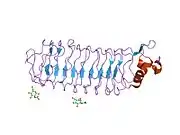

Reticulon 4 receptor (RTN4R) also known as Nogo-66 Receptor (NgR) or Nogo receptor 1 is a protein which in humans is encoded by the RTN4R gene.[5] This gene encodes the receptor for reticulon 4, oligodendrocytemyelin glycoprotein and myelin-associated glycoprotein. This receptor mediates axonal growth inhibition and may play a role in regulating axonal regeneration and plasticity in the adult central nervous system.[5]

The Nogo-66 Receptor (NgR) is a high affinity binding receptor for a region of Nogo, a myelin associated protein that inhibits axon outgrowth. NgR was identified by Strittmatter and colleagues[6] using an expression cloning strategy.

While the entire pathway is not fully understood, the relationship between NgR and neuronal outgrowth has been fleshed out. NgR is a membrane protein that, when bound to neurite outgrowth inhibitor (Nogo), inhibits cell growth through the activation of rho kinase (ROCK).